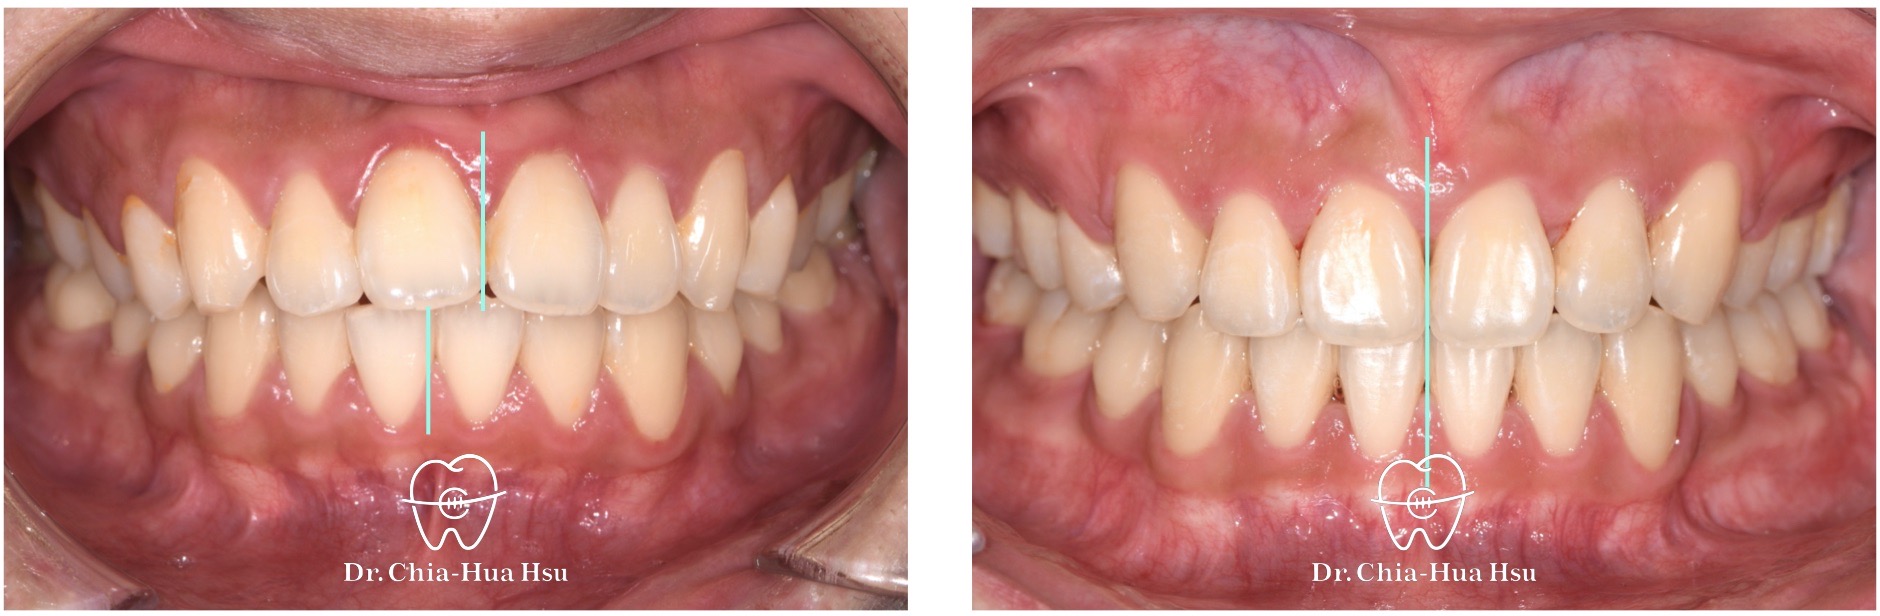

- 風趣幽默的20歲黃同學因為暴牙來院求診,由於患者下巴後縮又暴牙屬於複雜困難病例,還好病人十分配合療程,在許醫師悉心治療下,經歷兩年左右,讓治療順利完成。

- 病患主訴:暴牙、嘴凸、中線歪斜。

- 問題分析:患者是嚴重的骨骼二類咬合(Skeletal Class II)、下巴後縮、暴牙以及齒列不整齊。

- 治療方式:使用傳統金屬矯正器,並拔除四顆小臼齒,配合多支暫時性迷你骨釘來完成治療。

- 治療時間:2 年 2 個月。

- 治療結果:齒列排齊,外觀明顯改善,笑容更自信。

治療前

治療後